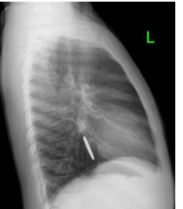

适用于金属或高密度异物,胸、腹部正侧位X线片可了解异物数量、大小、形态及位置,硬币类圆钝消化道异物需随访X线,以观察异物的位置,是否存在嵌顿的情况。

正侧位显示硬币的位置位于上消化道

腹腔异物(硬币) 腹腔异物(铁丝)